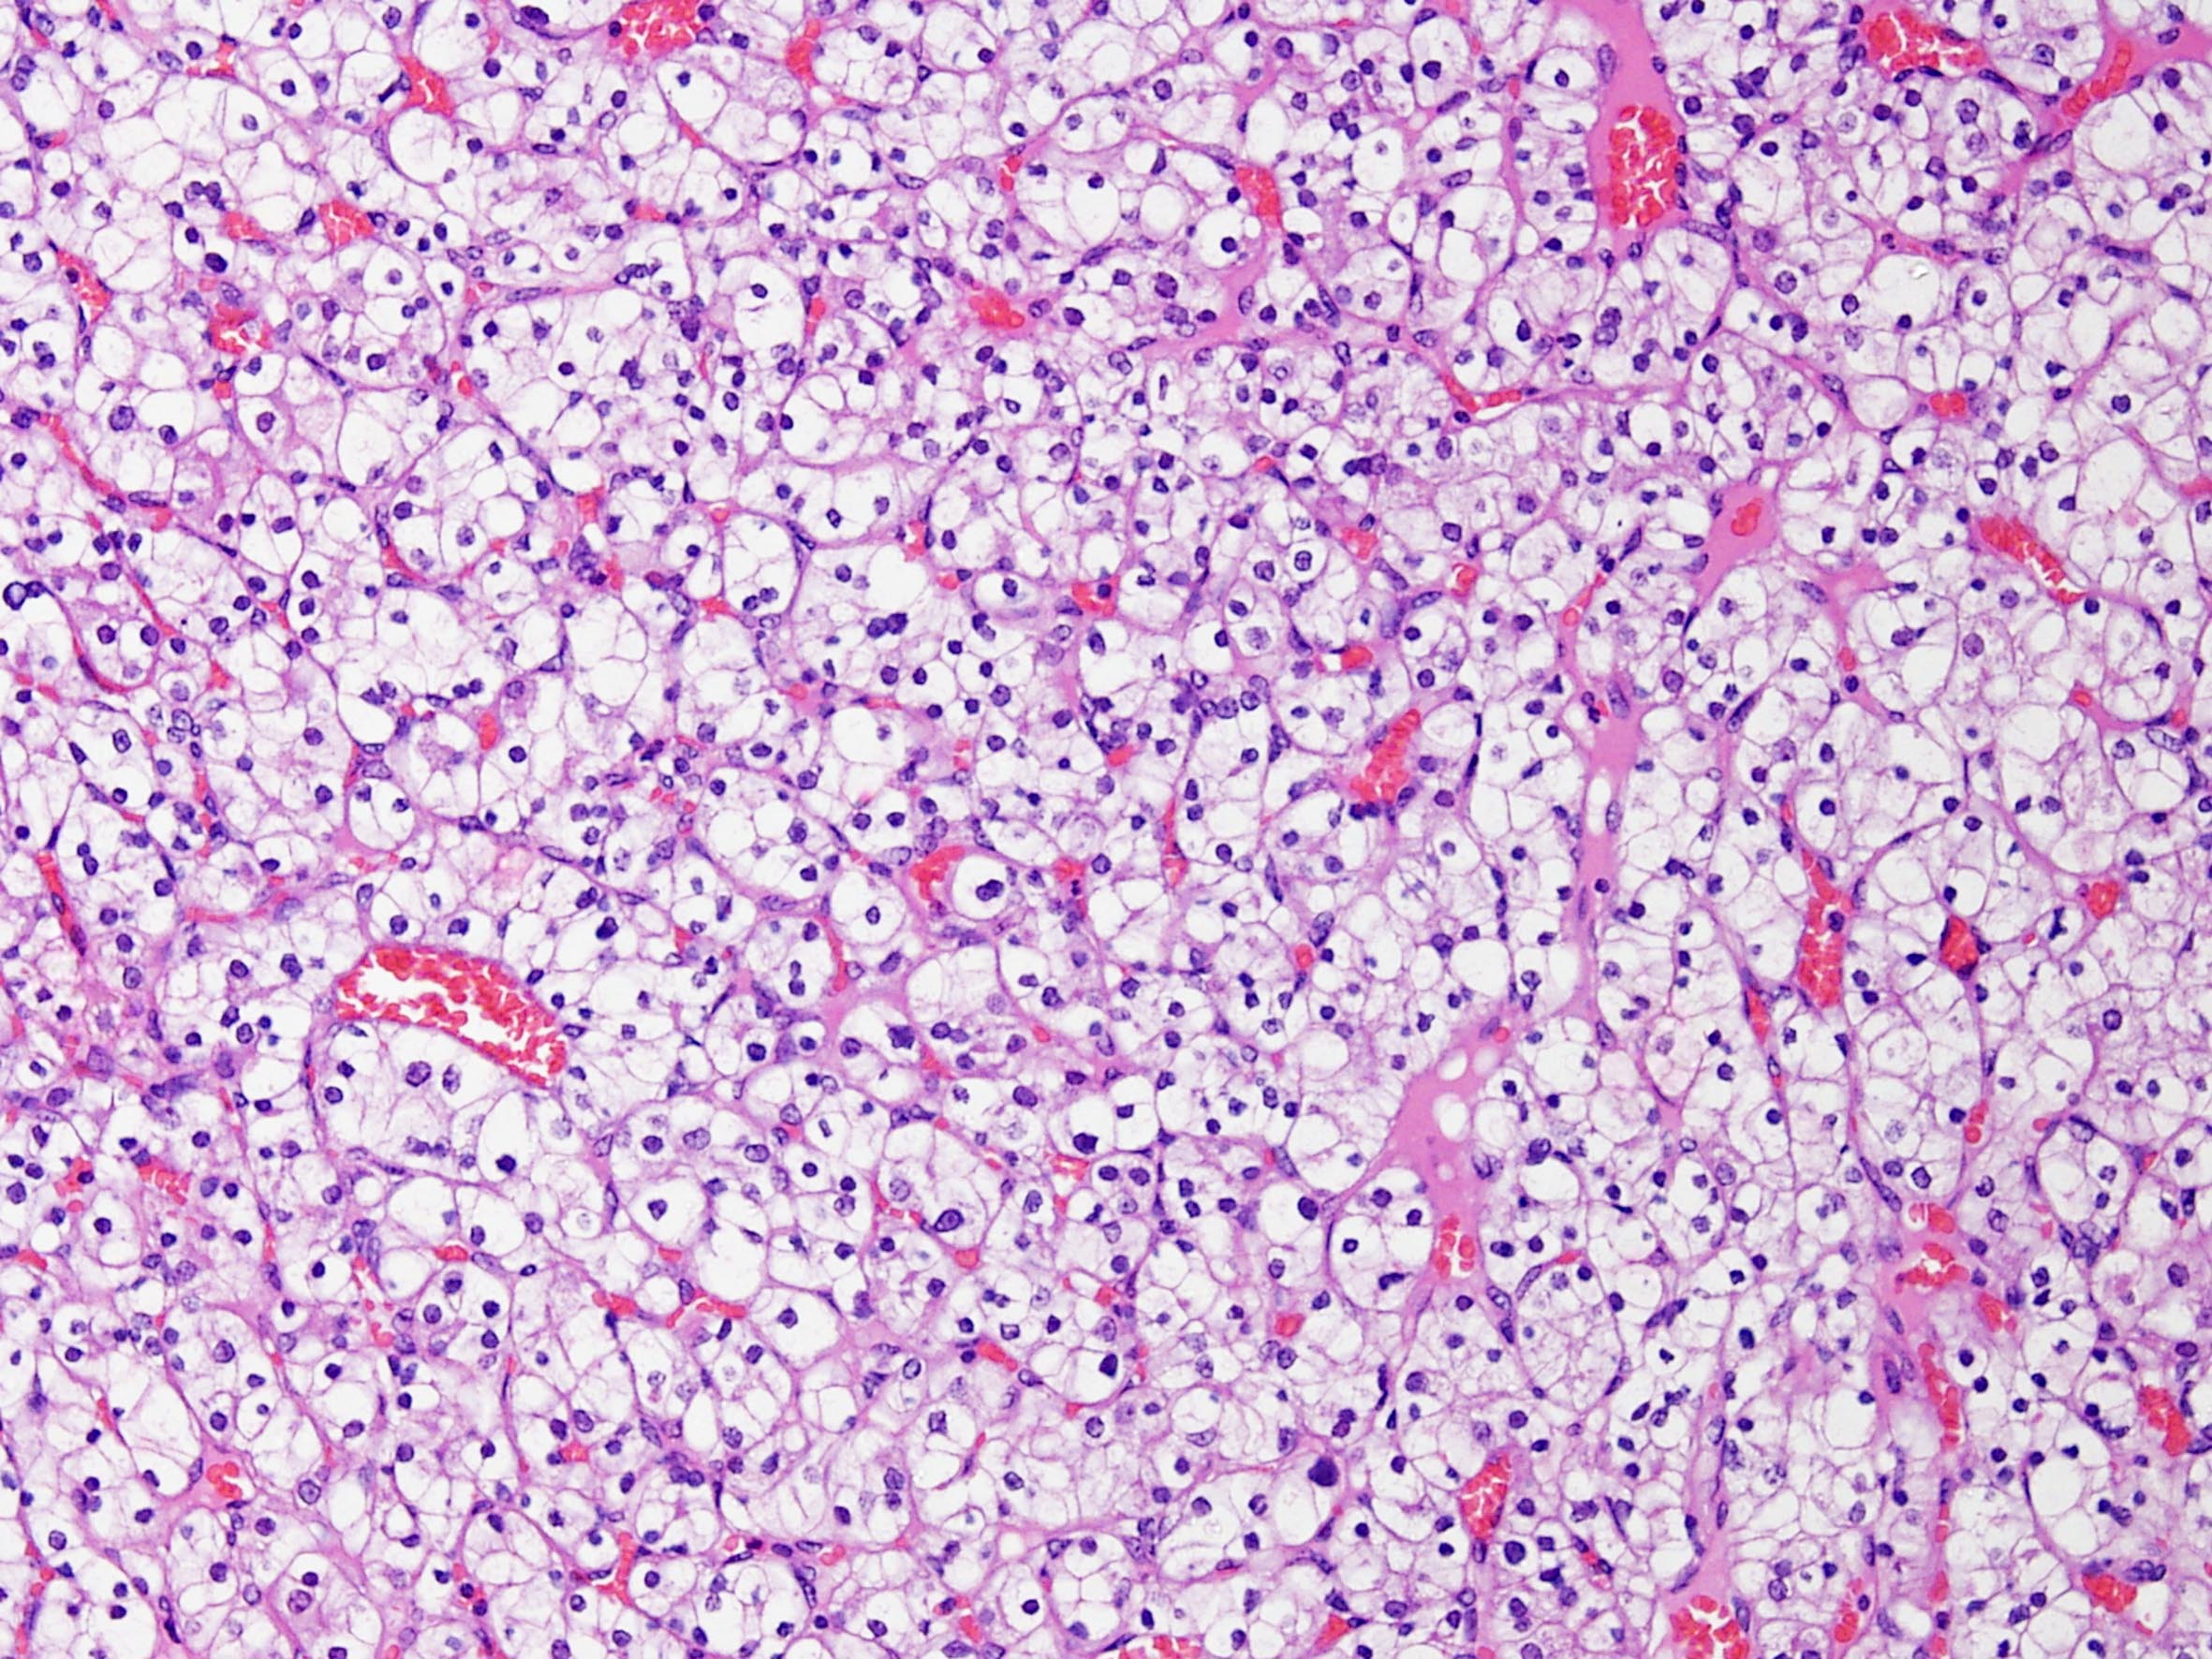

Classification of renal tumors

Case ID: 184